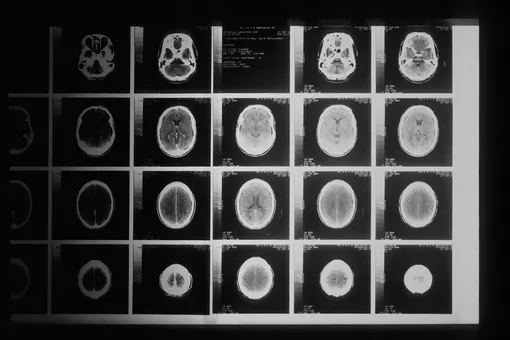

Команда из Королевского колледжа Лондона выяснила, что у людей с шизофренией в мозге снижен уровень железа и миелина – вещества, которое изолирует нервные волокна. Эти отклонения нарушают передачу сигналов между областями мозга и могут объяснять проблемы с мышлением и поведением. Главная причина, по мнению ученых, – сбои в работе клеток, отвечающих за производство миелина. Они не усваивают достаточно железа, а значит, не создают нужную «изоляцию» для нейронов.